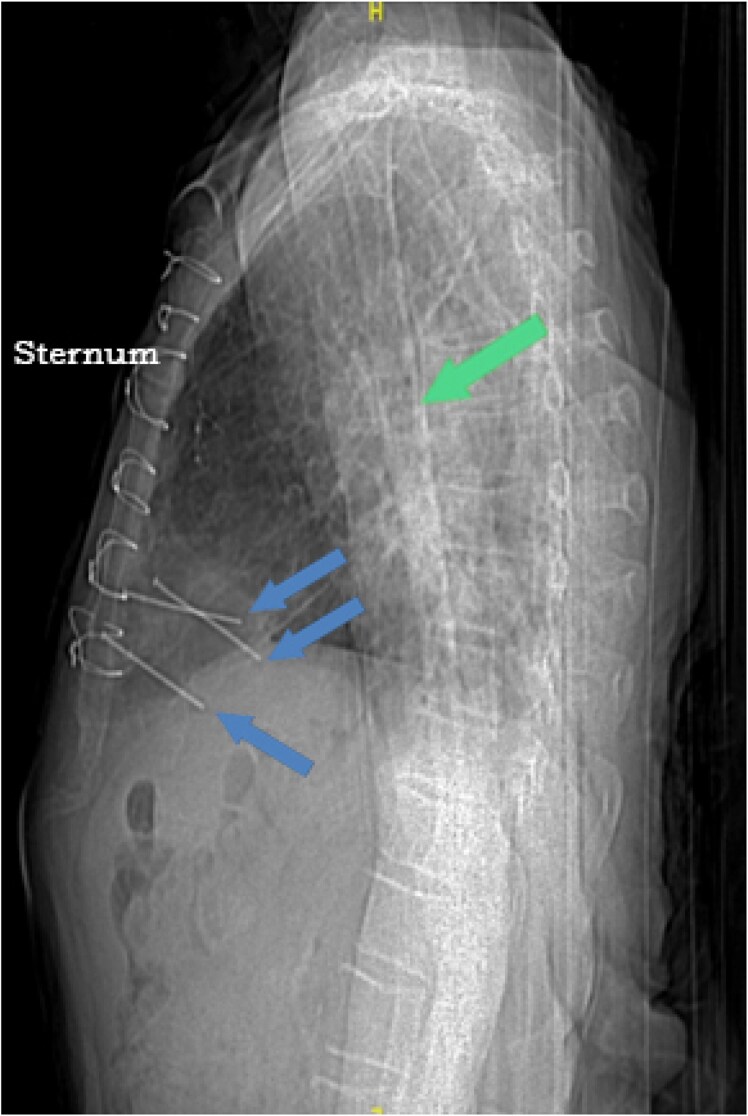

Case summary: A frail 83-year-old male who had undergone coronary artery bypass grafting surgery 20 years ago presented with encephalopathy. He had persistent bacteraemia. Chest computed tomography revealed three metal nails penetrating the anterior thoracic wall through the myocardium. Later, we learned that he had attempted suicide 2 years ago by shooting himself in the chest using a nail gun. Conservative non-surgical approach was pursued at that time given his multiple comorbidities. We adopted a conservative approach again. He survived for additional 6 months on chronic suppressive antimicrobial therapy but ultimately passed away from pneumonia.